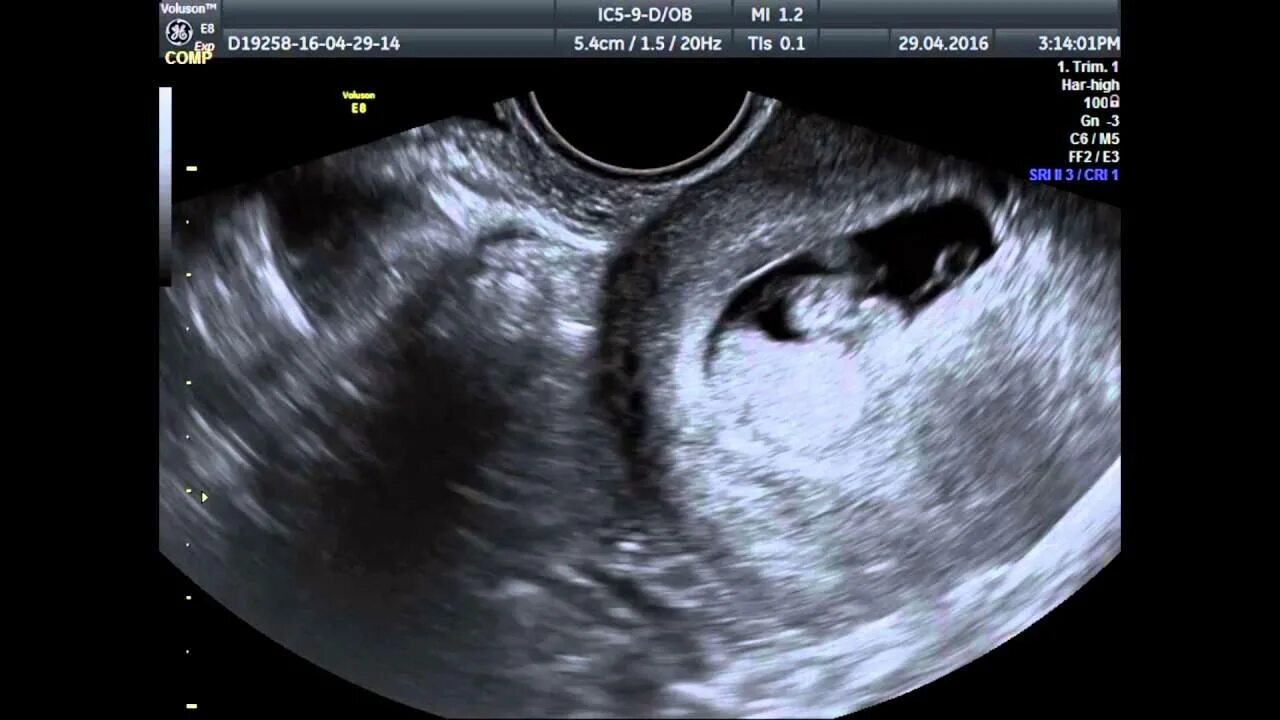

7 недель беременности симптомы